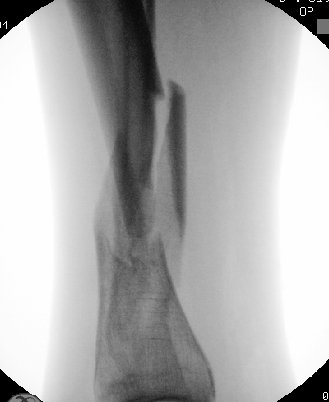

Midshaft #clavicle nonunion prediction at 6 wks post-injury appears superior to time of injury. We found 3 simple clinical predictors can accurately predict #fracture healing in most cases. This months @jbjs / jbjs.org/issue.php from our unit @EdinburghTrauma